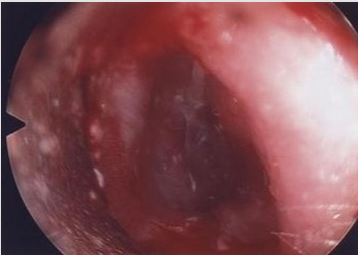

Six patients were identified: 66% (n=4) were male and 33% (n=2) were female. The female patients were twin sisters. Initial age at presentation ranged from 5 months to 4 years. 2 patients presented with X-linked ichthyosis. All patients had similar clinical presentations and clinical findings: hearing loss with no history of otorrhea or ear infections. Type B tympanograms and hearing loss was recorded. Otoacoustic emission (OAE) and middle ear reflexes (MER) were within normal range in all patients post procedure. All patients were booked for examination under general anesthesia (EAU). This revealed ear canal keratin plugs with some inflammatory skin changes in the absence of infective otitis externa or middle ear disease (Figures 1-3). Post operatively patients were reviewed in the outpatient department (OPD) at six weeks. If early ear canal keratinisation was observed at this time patients were commenced on olive oil ear drops and were re-scheduled for a second EUA and microdebridement of ears at a three-month interval. Preoperative tympanograms were type B. EUA results were similar demonstrating keratin plugs which underwent microdebridement. Post-operative tympanogram were within normal ranges.